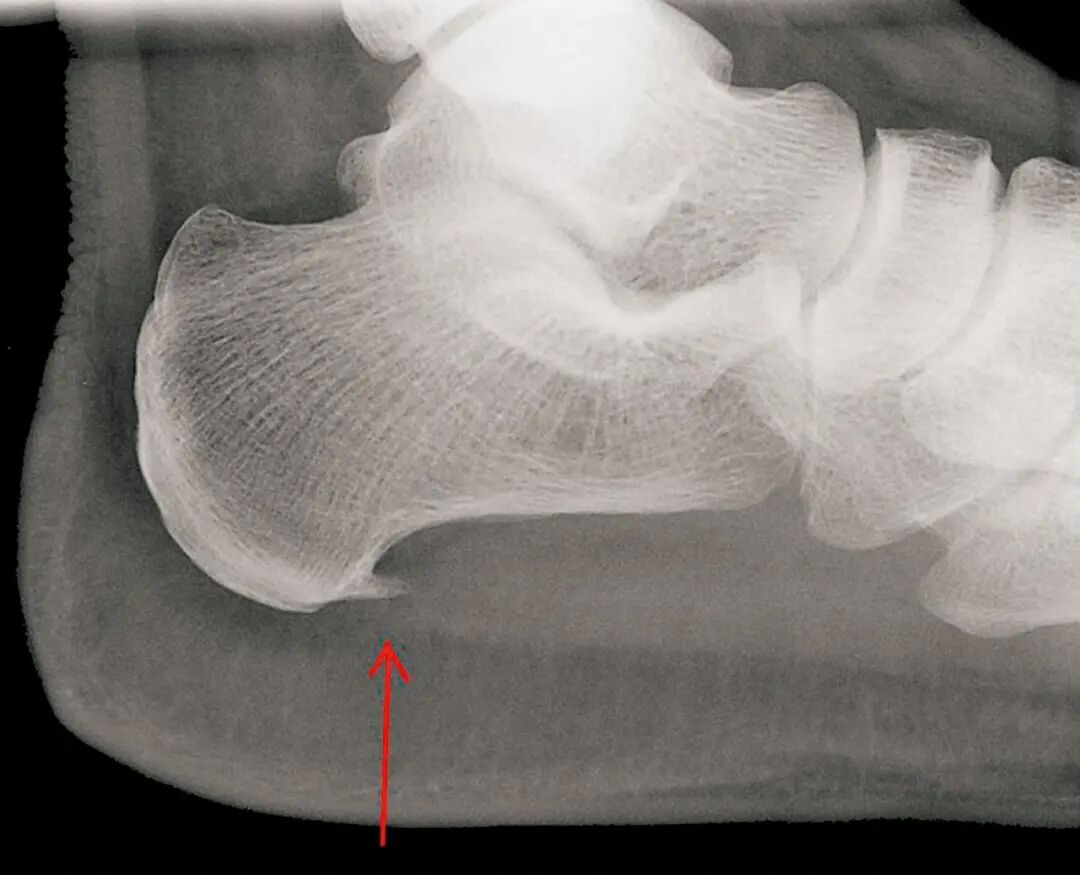

骨刺像一块多余的“石头”,在关节活动时反复摩擦、撞击周围的肌腱、韧带或滑囊(充满液体的减震小囊),引起局部酸痛、肿胀、活动受限。例如:跟骨骨刺刺激足底筋膜附着点 → 足跟痛(足底筋膜炎,骨刺常是结果而非唯一原因)。 膝关节边缘骨刺摩擦周围软组织 → 膝关节疼痛、弹响。